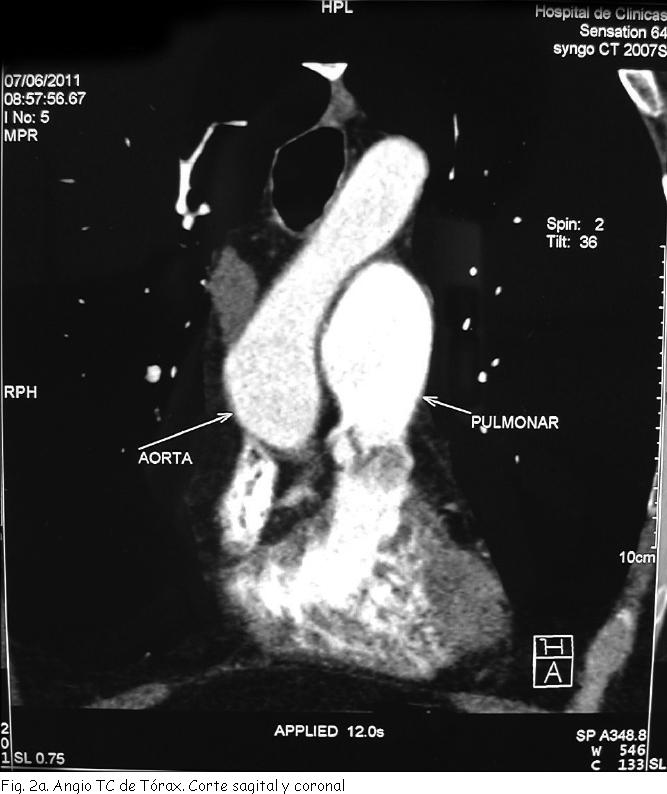

AngioTC y angioRNM de Tórax: dilatación aneurismática fusiforme de rama izquierda de arteria pulmonar de 42 mm de diámetro máximo que compromete toda su extensión (Figura 2 a, 2b).